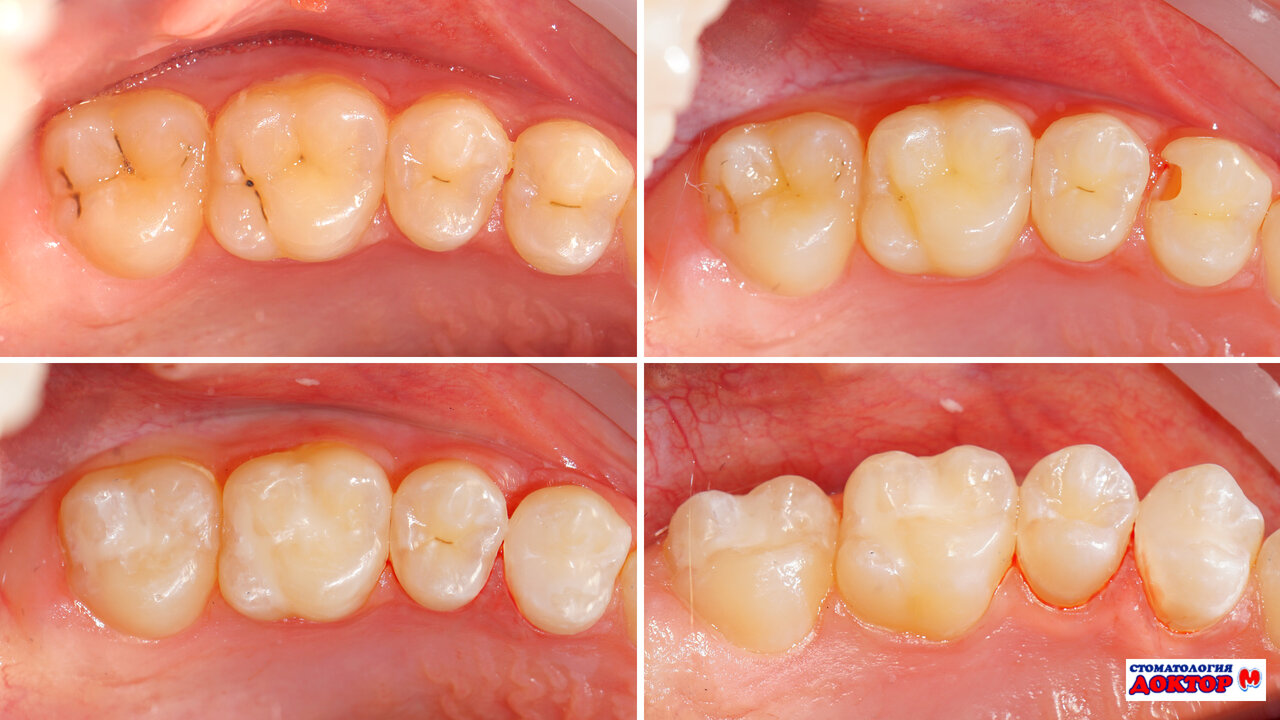

Среди основных направлений работы: лечение кариеса, пломбирование, удаление зубов, протезирование, установка виниров и коронок, а также профессиональная гигиена. Отдельное внимание уделяется эстетической стоматологии, включая отбеливание и реставрацию зубов. В клинике проводятся сложные процедуры, такие как лечение периодонтита, кисты зуба и эндодонтическая терапия.

- Фотофиксация этапов лечения.

Рустама Робертовича мне порекомендовала стоматолог из другого города, лечение прошло на высшем уровне! Большое спасибо за проведенную обьемную и качественную работу, отношение к пациенту самое внимательное и чуткое, подробно все рассказывает, показывает, каждый шаг в лечении фотографирует. Одним словом профи, и такие же медсестры!